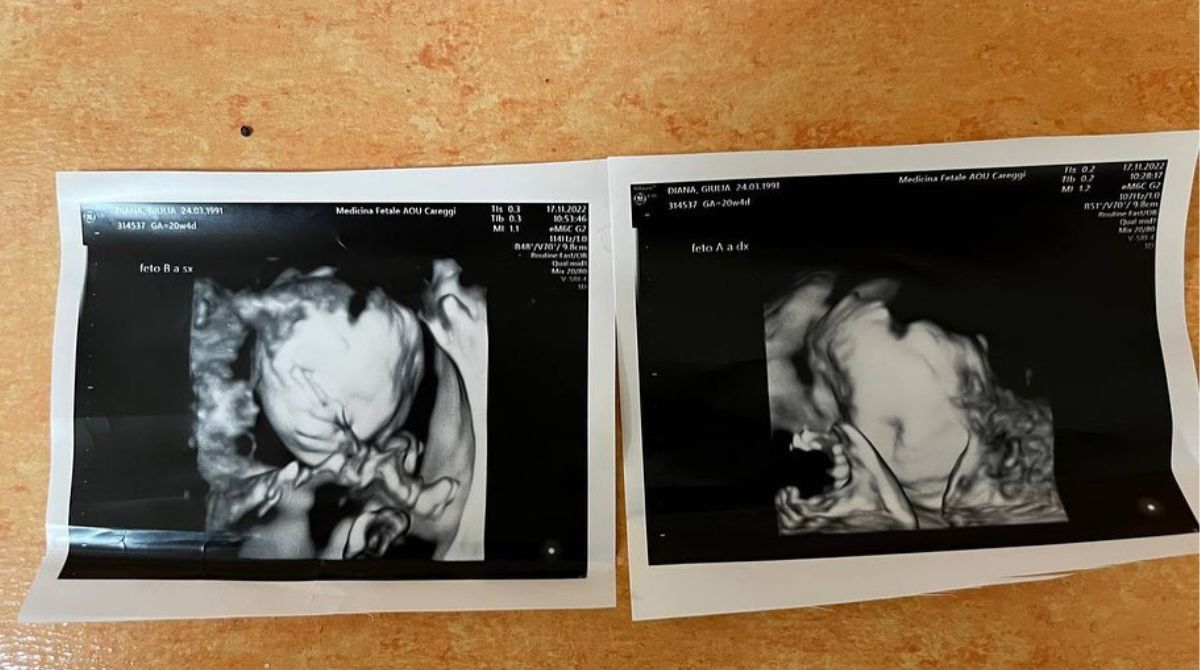

Enrico Nigiotti diventà papà e lo annuncia con un tenero post pubblicato sul suo profilo Instagram. Il cantante 35enne, originario, di Livorno ha dato il lieto annuncio scrivendo direttamente ai suoi figli. “È tutto un conto alla rovescia verso di voi” ha scritto sotto una foto che ritrae il pancione della compagna Giulia Diana, le ecografie e due tutine.